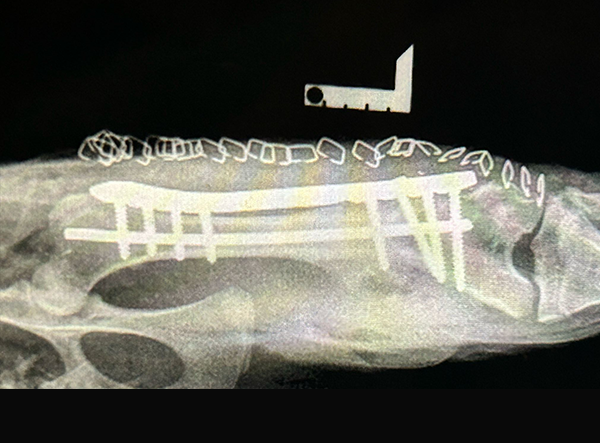

The femur fracture was surgically treated by Dr. Matan Or, using a 3.5 LeiLOX Locking Bridge Plate to provide stable fixation and support the healing process. The LeiLOX system is designed to offer reliable stability while minimizing soft tissue disruption, which is crucial for optimal recovery and a safe return to natural mobility. Its locking mechanism ensures strong fixation, and the bridging technique helps maintain blood supply to the bone, supporting natural bone regeneration.

• Secure Stability: Rigid fixation for reliable fracture healing.

• Tissue-Friendly: Minimizes soft tissue disruption.

• Supports Healing: Promotes natural bone regeneration.

Implant Used:Â 3.5 LeiLOX Bridge Plate - Stainless Steel

System: LeiLOX Locking System

Manufacturer: Rita Leibinger Medical

Surgery by: Dr. Matan Or (Israel)